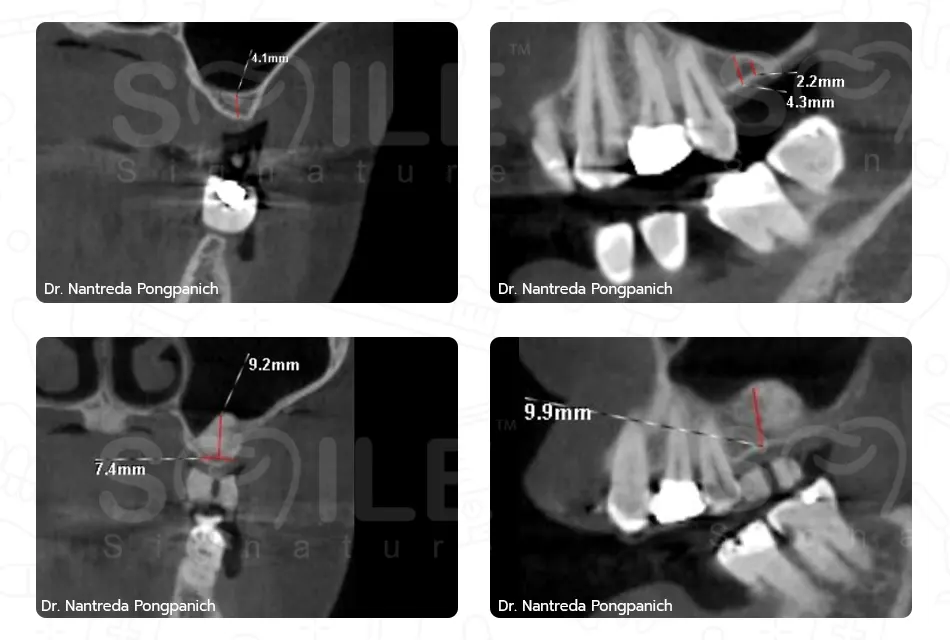

Image Box text